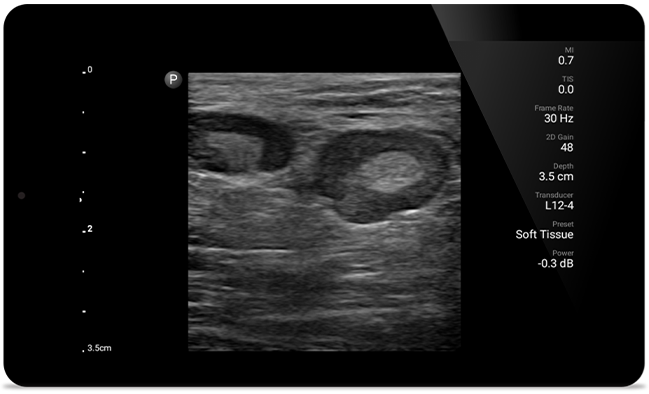

Lumify helpt u de fijne details in spieren, gewrichten, ligamenten, pezen en kraakbeen te zien om een nauwkeurigere diagnose te kunnen stellen.

Lumify kan u helpen patiënten van top tot teen te beoordelen, of het nu gaat om fasciitis plantaris, tendinitis of bursitis in de ligamentum patellae, of zelfs schouderinstabiliteit in de rotatorenmanchet.

SonoCT versterkt de beeldvorming van het echte weefsel, terwijl willekeurige artefacten worden geëlimineerd. Deze technologie produceert beelden die beter zijn dan conventionele beeldvorming bij tot wel 94% van de patiënten.